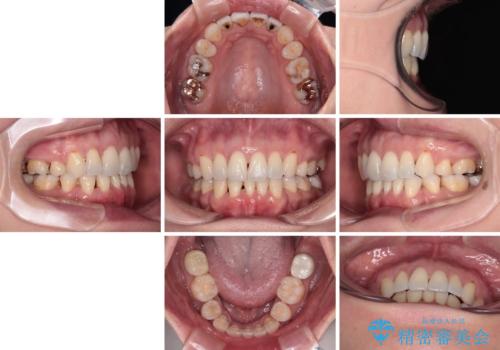

当初目論見通り、左右奥歯の咬み合わせはしっかりとさせることができました。

下唇に跡がつくほど飛び出していた上顎前歯も引っ込み、満足のいく仕上がりとなりました。